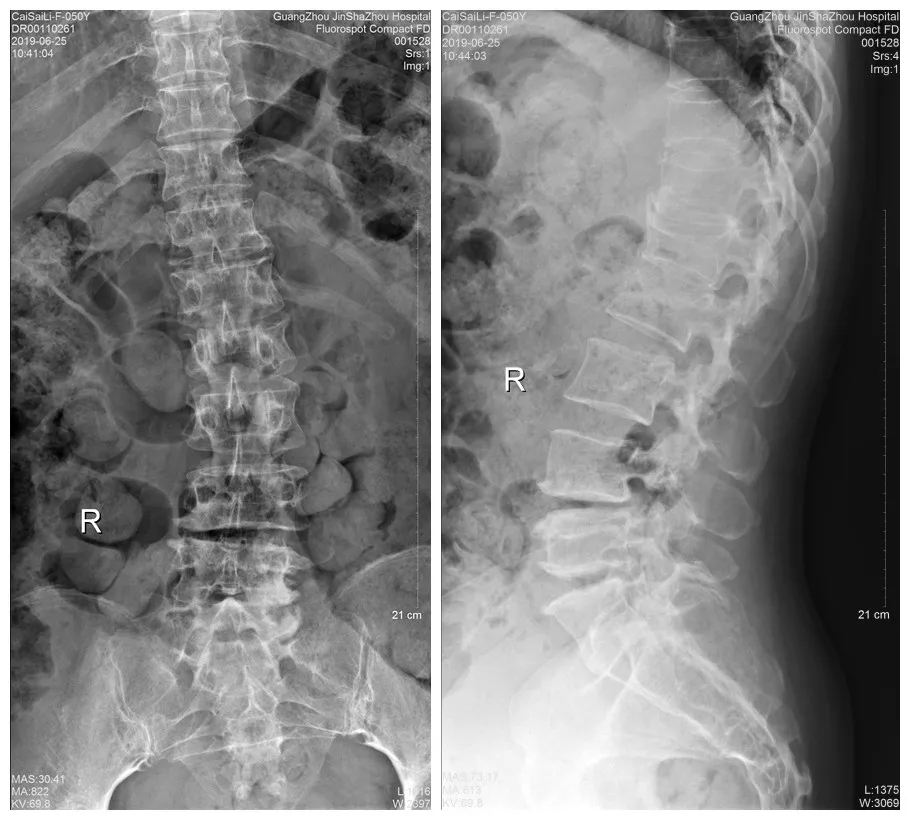

术前DR

于是经朋友介绍,蔡阿姨来到了我们金沙洲医院骨科中心求诊。经检查提示腰2椎体压缩性骨折,腰椎峡部裂。由于蔡阿姨的骨折和腰椎突出情况比较复杂,经过对蔡阿姨病情的详细评估,骨科中心分二次给蔡阿姨进行了手术。在我们见到蔡阿姨的时候,她第二次手术已经结束,除了下肢尚有一点点麻痹,医生说她其他方面恢复得很好,她看起来精神也不错。